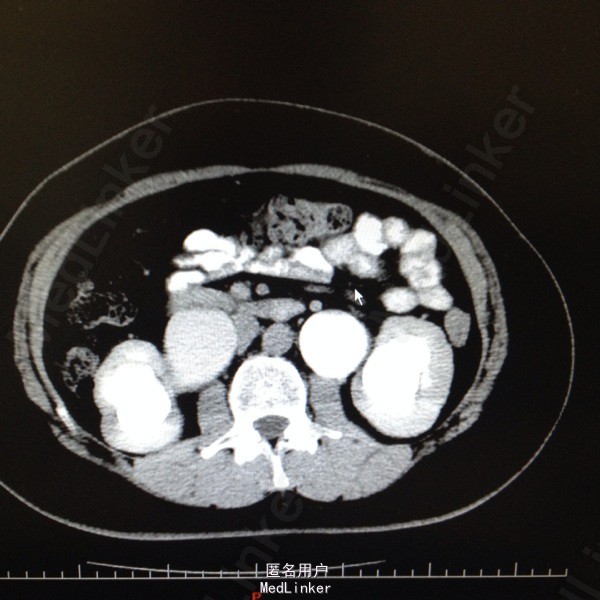

47岁女患。 病史:患者6年前因宫颈癌行全子宫及双侧附件切除。盆腔淋巴结清扫。腹主动脉旁淋巴结活检术。后又行局部放疗。因双肾积水来我科。患者自述平时轻微排尿困难,尿线细。

双肾区无叩击痛,双输尿管走形区无压痛。耻骨上区隆起,叩诊浊音。排尿后留置尿管引流尿液400ml。 辅助检查:肌酐99。 ct:双肾及输尿管积水。 留置尿管后一周泌尿系彩超:双肾积水明显减轻。具体见图片。

诊断:双肾及双输尿管积水 神经源性膀胱 给予患者留置尿管后1周行泌尿系彩超检查肾积水减轻。